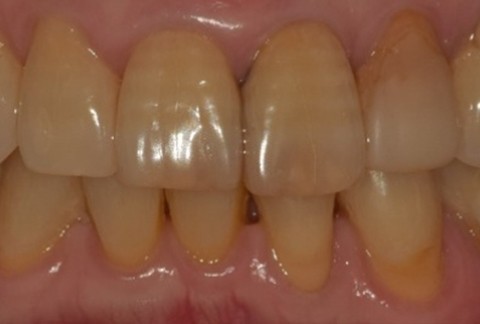

임플란트-전후사진